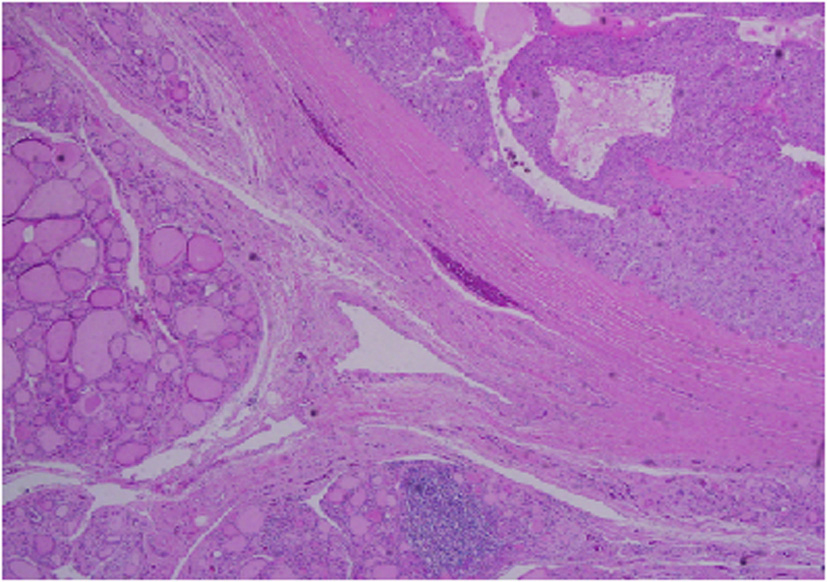

Architecturally, the lesion shows a solid to trabecular growth pattern and is associated with hemorrhage and hemosiderin deposition (Fig. 4). In addition, there are foci highly suspicious for lymph-vascular invasion, and the lesion appears to be poorly encapsulated, with islands of tumor separated by thick fibrous bands (Fig. 5). Morphologically, the cytoplasm is clear to amphophilic, with prominent and distinct cell borders. The background cells have monotonous nuclei with neuroendocrine “salt and pepper” chromatin (Fig. 6). The cells of concern range from moderately pleomorphic to wildly atypical and have irregular nuclear contours. In many areas multinucleation is identified. The nucleoli range from inconspicuous to prominent with cherry-red eosinophilia, irregular membranes and peri-nucleolar halos, the latter being a feature almost exclusively seen in PCA [12] (Fig. 7). The sum total of these findings supports a diagnosis of intrathyroidal parathyroid carcinoma (Fig. 8, 9). In this case, the hypercellular parathyroid tissue noted in several of the sections is morphologically distinct from the predominant neoplasm, interpreted as carcinoma (Fig. 9).

![]() Click for large image | Figure 8. Low power view showing parathyroid carcinoma (upper right) and adjacent thyroid tissue (lower left). |

![]() Click for large image | Figure 9. Medium power view of parathyroid carcinoma showing marked nuclear pleomorphic in the background of more typical parathyroid tissue. |